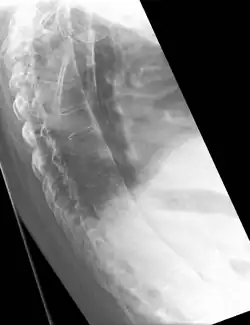

Lateral X-ray of the mid back in ankylosing spondylitis -